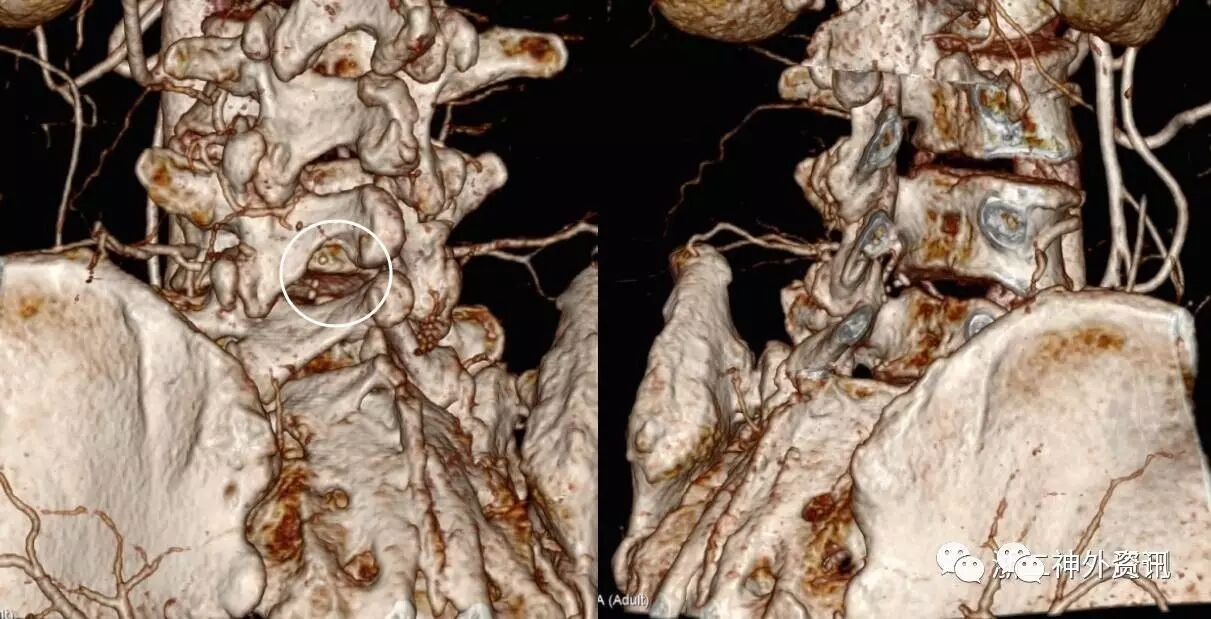

进一步行DSA检查,用 C2导管依次行胸12-腰4双侧肋间动脉、双侧腰动脉造影,见瘘口位于腰4椎体水平,由左侧腰4腰动脉供血,通过髓周静脉引流,并见引流缓慢,髓周静脉迂曲。造影诊断:硬脊膜动静脉瘘(图3)。

图3. DSA检查显示瘘口(白色箭头所示)位于腰4椎体水平,左侧腰4腰动脉的分支由腰5椎间孔进入椎管。